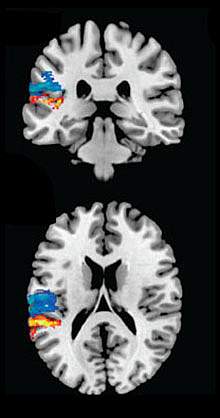

The scientists identified 2 major divisions in the way the language system is organized, resulting in 4 factors: the meaning versus the form of words, and speech recognition versus production. They next examined high-resolution MRI or CT brain scans of the participants to map the location of their lesions with their symptoms.

The researchers found that the 4 factors were associated with various lesion areas. For example, speech production and speech recognition were associated with damage to adjacent regions. Whereas some factors were linked to distinct brain regions, others converged, suggesting that certain areas might have broader functional significance.